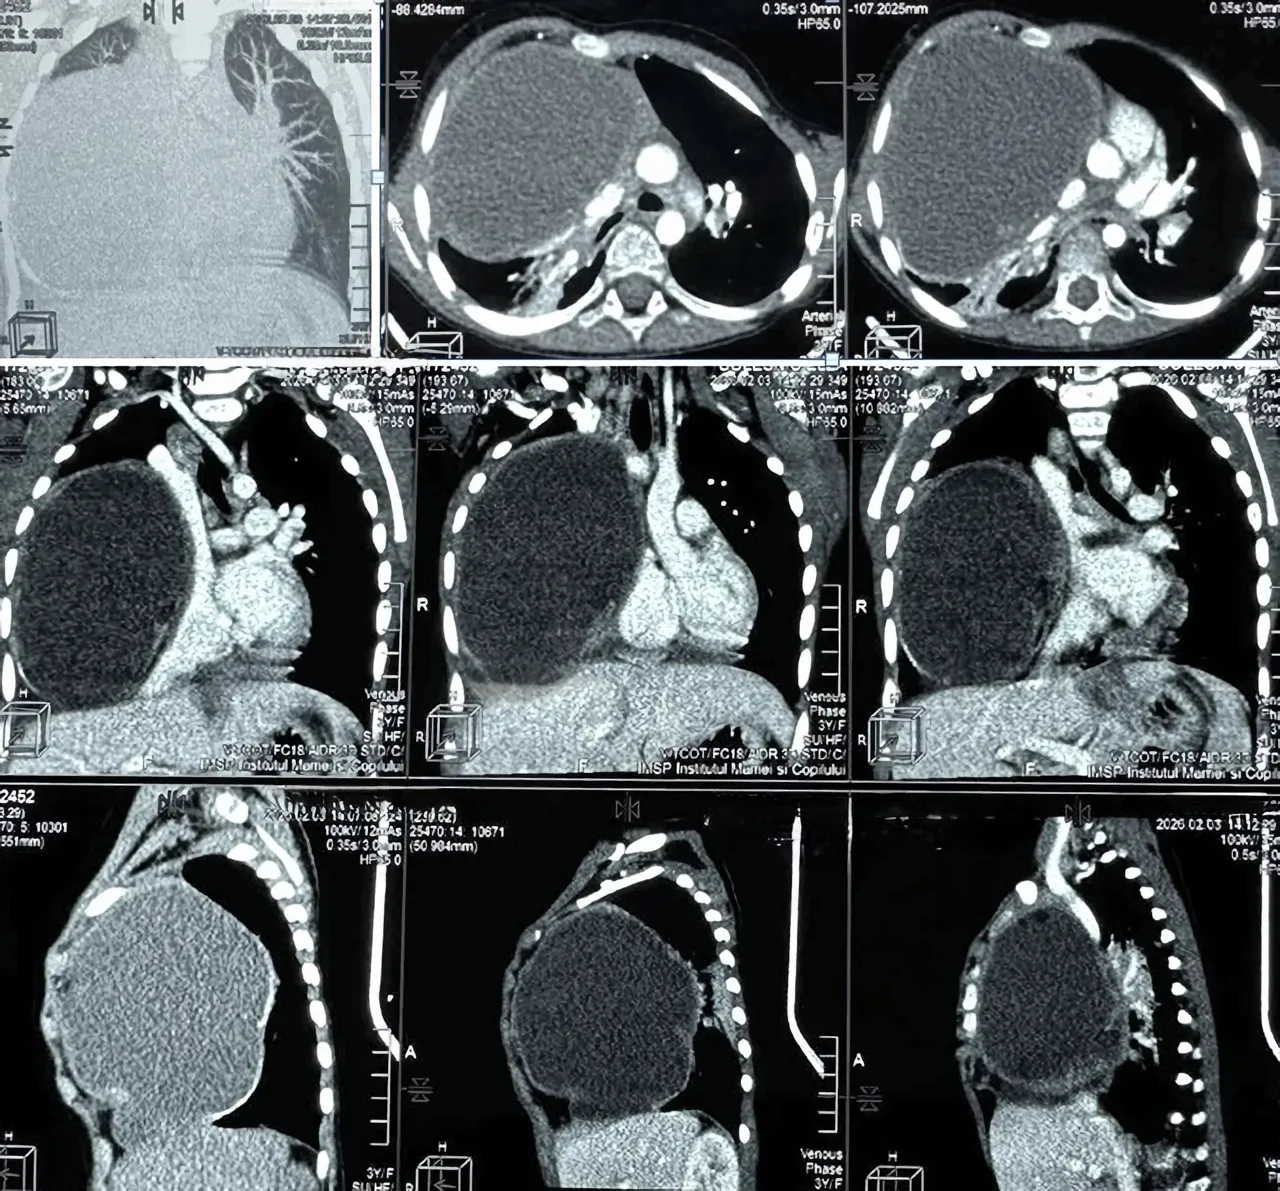

Investigațiile imagistice efectuate în cadrul serviciului de radiologie și medicină nucleară au arătat o situație gravă: o formațiune tumorală de aproximativ 12 x 9 x 10 cm, localizată în hemitoracele drept. Potrivit medicilor, tumora ocupa circa 80% din cavitatea pleurală, comprimând aproape în totalitate plămânul drept și exercitând presiune severă asupra structurilor mediastinale.

Tomografia a sugerat un caracter multicomponențial al formațiunii, cu suspiciune de teratom, fiind menționată și asocierea cu o anomalie vasculară rară – artera subclavie dreaptă aberantă.